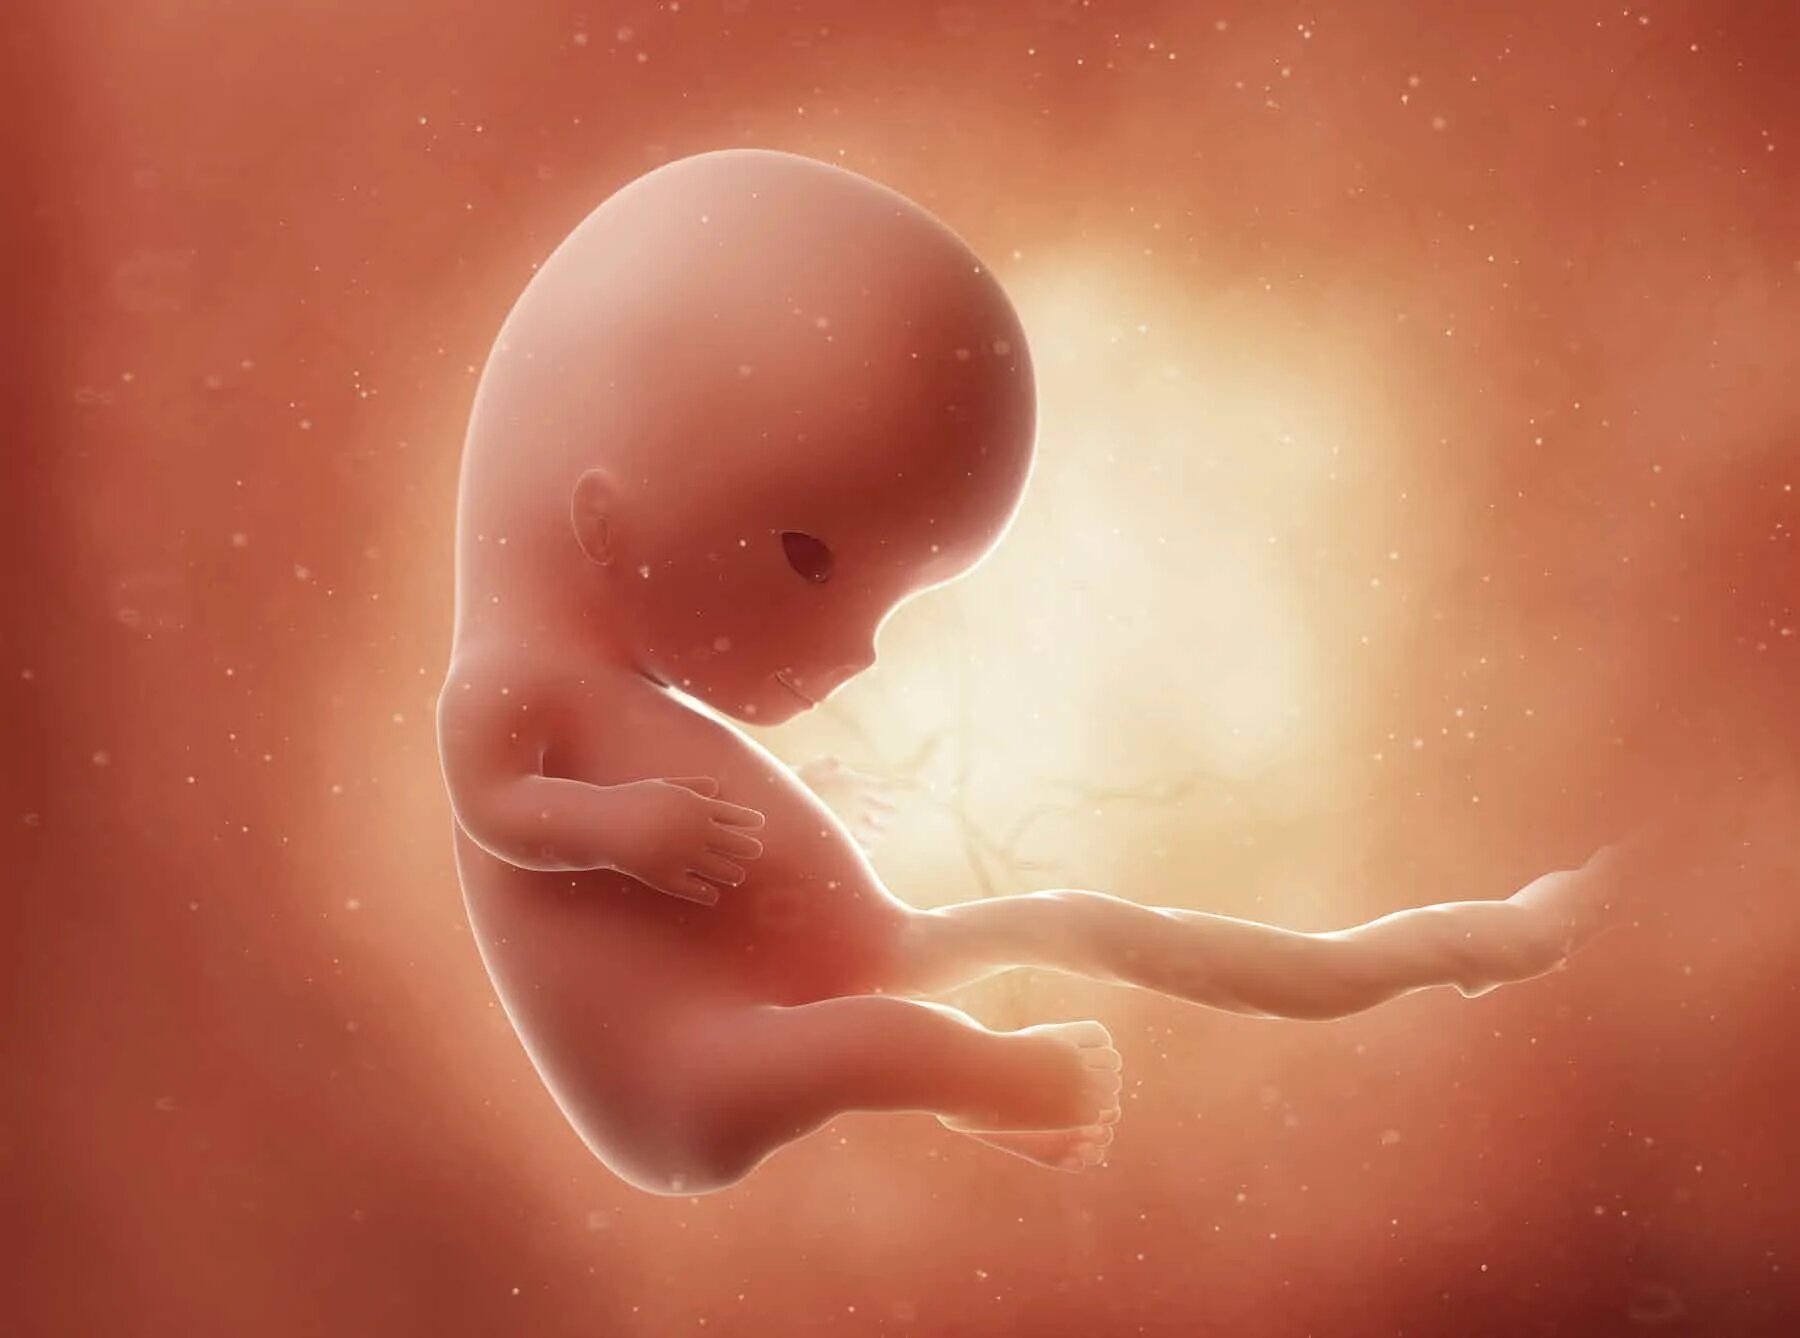

1 9 неделя беременности